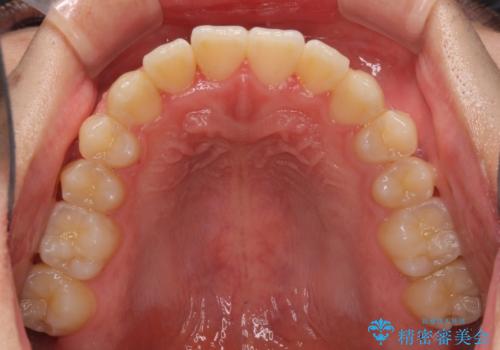

- 上下前歯のデコボコを気にして来院された患者様です。

叢生は軽微であり、費用を抑えて期間もあまりかけずに治療をしたいとのことで、インビザライン・ライトを用いて矯正治療を行うこととしました。

途中通院できなくなり、マウスピースの装着もしっかりとできなかったため、治療期間が長くかかってしまいました。